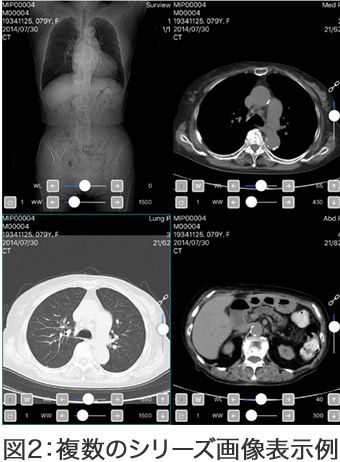

画像参照のUIツール:図2

- 異なる検査日のシリーズを複数同時表示

- シンクロ機能